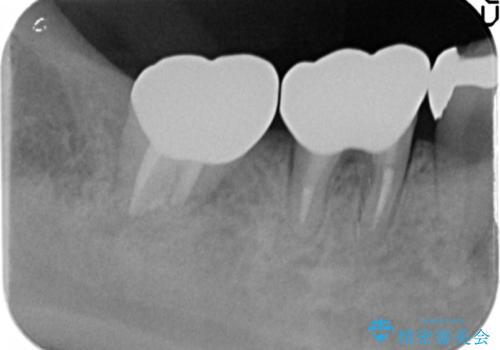

根管治療 → リトリートメント

金属をセラミックにしたい、根管治療も行ったケース